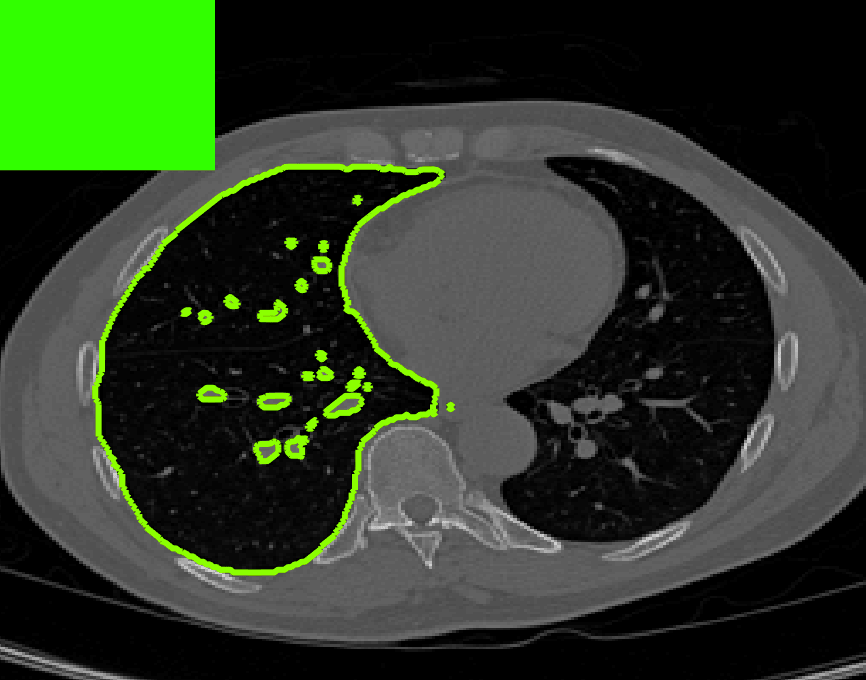

The motivation for this work comes from observing contradictions in using piecewise-constant intensity fitting terms in selective segmentation. Whilst good results are possible with this approach, the exceptional cases lead to severe limitations in practice. This is quite common in medical imaging as demonstrated in Fig. 1, where the target foreground has a low intensity. Given that the corresponding background includes large regions of low intensity, the optimal average intensities for this segmentation problem are and . For cases where , we see that by (1), almost everywhere in the domain . This means that it is very difficult to achieve an adequate result, without an over-reliance on the user input or parameter selection.

where is noise, is the characteristic function of the region , for respectively. The idea of selective segmentation is to incorporate user input to apply constraints that exclude regions classified as foreground, based on their location in the image. We use a distance constraint which penalises the distance from the user input markers. However, a key problem for selective segmentation is that for cases where the optimal intensity values and are similar, the intensity fitting term will become obsolete as the contour evolves. This is illustrated in Fig. 3. The purpose of our approach is to construct a model that is based on assumptions that are consistent with the observed image and any homogeneous target region of interest. A common approach in selective segmentation is to discriminate between objects of a similar intensity Rada:13 ; Geo ; CDSS . However, the fitting terms in previous formulations Klodt:13 ; Rada:13 ; Geo ; CDSS aren’t applicable in many cases as there are contradictions in the formulation in this context. We will address this in detail in the following section.

[\capbeside\thisfloatsetupcapbesideposition=left,top,capbesidewidth=1.5in]figure[\FBwidth]

for and as defined in (33). This is consistent with respect to the intensities of the observed object and the concept of selective segmentation. In Fig. 3 we see the difference between CV and the proposed fitting terms for given user input on a CT image. For the CT image, the CV fitting terms are near 0 within the target region. This is despite there being a distinct homogeneous area with good contrast on the boundary. This illustrates the problem we are aiming to overcome. With the proposed fitting term this phenomenon should be avoided in cases like this. By defining as in (33) there is no contradiction if the foreground and background intensities of the target region are similar.